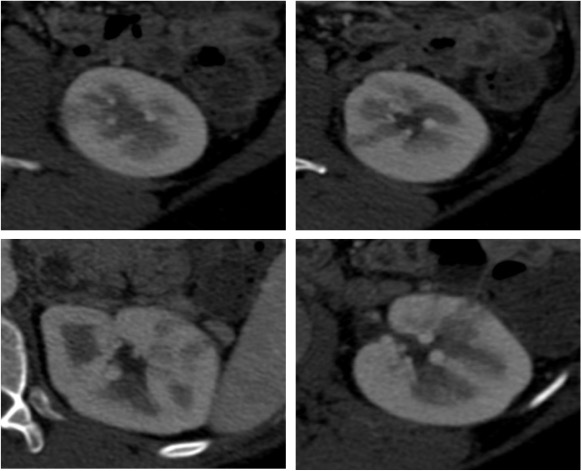

Se procede a realizar TC abdomino-pélvico con contraste en fase nefrográfica y excretora:

Conclusión: se nos presentó un caso de un paciente con una sospecha de infección renal complicada ya que tras cuatro días de tratamiento antibiótico no hubo mejoría. Ante los hallazgos observados en TC, podemos establecer el diagnóstico de pieloureteritis renal izquierda con signos de hidroureteronefrosis leve hasta vejiga.

- Protocolo: TC abominopélvico sin y con contraste en fase nefrográfica (70 seg) +/- fase tardía ( a los 7 – 10 min) solo si se sospecha obstrucción.

- TC con contraste: Las áreas afectadas del parénquima aparecen como zonas con baja atenuación debido al edema. Las áreas hiperdensas son menos frecuentes y corresponden a focos de hemorragia. Estos hallazgos son mejor valorables a través de la aplicación de contraste, ya que un TC en vacío pueden pasar desaprecibidas.